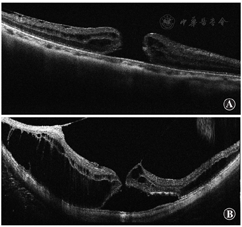

典型的OCT图像显示后巩膜葡萄肿内的视网膜内层和外层分裂,据此猜测,视网膜内层比外层柔韧性差[176]。限制视网膜内层柔韧性的因素包括玻璃体皮质黏附于视网膜上、视网膜前膜、内界膜和视网膜血管。视网膜前膜在高度近视中通常很难识别,但显微镜下可分辨[177]。任何一种或所有的这些因素都会降低视网膜的柔韧性。

(1)症状 患者通常能感受到中央视物变形,这与视网膜劈裂位置和视网膜脱离导致的相对暗点对应。当视网膜脱离区内的黄斑裂孔裂开时,患者可能在相对暗点中心感觉到有1个绝对暗点。如果伴有广泛的视网膜脱离,患者也会感觉到受累区域的视野缺失。对于视网膜脱离区域内的黄斑裂孔,Watzke-Allen试验通常呈阴性。(2)眼底及OCT表现 在高度近视眼中,近视黄斑裂孔表现为后部视网膜的轻微隆起;然而,OCT对于准确诊断是必不可少的,特别是在萎缩的眼底。OCT不仅对全面评估视网膜的状态至关重要,而且对手术决策也至关重要。近视黄斑裂孔表现为多个层次的视网膜劈裂(图11)。在分裂的视网膜各层之间通常有一些连接物,即所谓的柱,推测这是残存的Müller细胞[179]。内界膜也可以与其他视网膜层分离,即所谓的内界膜脱离(图12A),这是来自视网膜内界膜牵引力的良好指标[180]。OCT图像上可以看到视网膜内层的帐篷状凸起。这一发现与视网膜血管和所谓的视网膜微血管牵引相一致,在玻璃体切割联合内界膜剥除手术后观察得更清晰(图12B)[181]。这种对视网膜血管的牵引力在高度近视眼中也可作为血管旁微孔被观察到[182]。光感受器的椭圆体带有时在视网膜脱离区也会消失[183];然而,椭圆体带在视网膜劈裂区通常保存完好。这一发现表明,光感受器的功能在这种亚型中保存良好。

根据OCT表现,黄斑裂孔形成前有2个阶段与视网膜劈裂相关(图13)。第1个阶段是视网膜劈裂型的发展阶段,在这个阶段中只有视网膜劈裂而没有视网膜脱离(图13A)[176]。几个月(有时几年)后,中央凹附近开始出现视网膜脱离。这一阶段称为中央凹脱离型(图13B)。一段时间后,脱离上方的内层视网膜被拉伸和撕裂。这就是视网膜劈裂伴视网膜脱离导致黄斑裂孔的原因。

高度近视有2种类型的黄斑裂孔(图14)[184]。一种类型是裂孔边缘增厚并伴有视网膜囊样改变(图14A)。临床上裂孔周围无视网膜脱离,这种类型通常数月或数年不发生变化。另一种类型是在裂孔周围环绕着视网膜劈裂,而不是视网膜囊样改变(图14B)。这种类型的黄斑裂孔是由近视性黄斑劈裂引起的,通常由于潜在的牵引力而进展迅速。